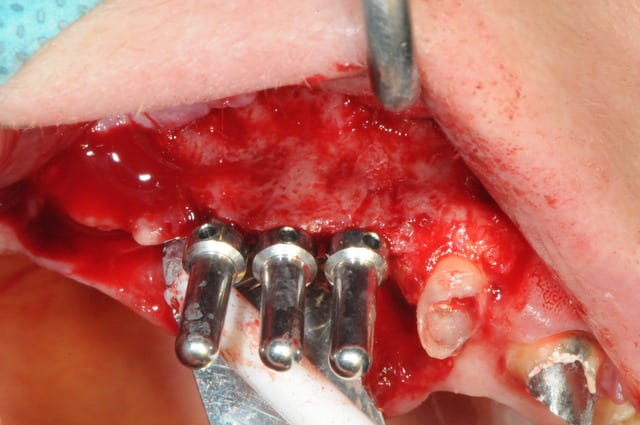

piges de contrôle et pose des implants après 2 heures d'expansion au syndesmotome et ostéotomes!

Anesthésie -

incision supra -crestal - décharge au niveau de 12-11 - lambeau pleine épaisseur- fenêtre d'accé au sinus- soulevé de la membrane de Schneider- comblement Graftec- membrane Collagen AT - spliting sur la crête osseuse de 15 à 12- légère décharge osseuse au niveau de 12 - expansion osseuse en vestibulaire- pose implants -13-14-15- comblement espace inter implants et en vestibulaire par KASIOS TCP - membrane de recouvrement Collagen AT-

Sutures simples vicryl 5/0 pour la décharge et 4/0 pour la crête.